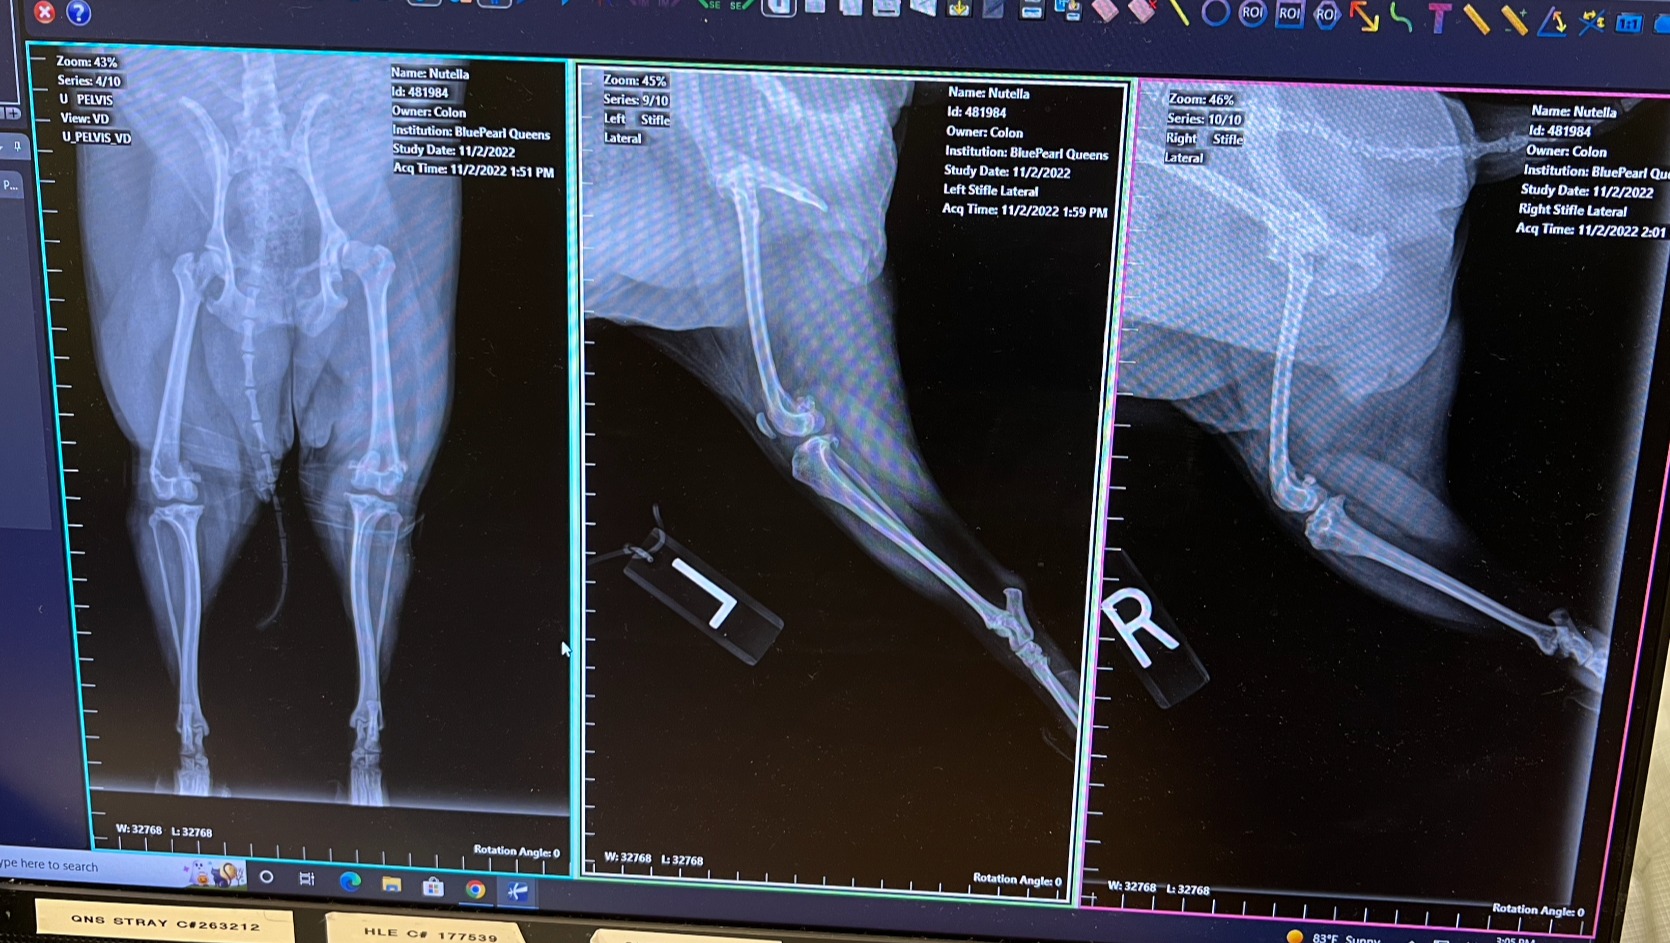

Hi, my name is Geraldine. I’m fundraising to save money for my dog Nutella so she can walk again. She had just celebrated her 3rd birthday on 10/25. Nutella is a loving, sweet girl, often mistaken for a little black bear. She loves to play around in the grass, fight with her older sister Bebecita, and do tricks for her favorite treats.

She suffers from multiple orthopedic issues and will need 3 surgeries to help repair her left hip (FHO), left cruciate ligament rupture, and right knee. She will need about 6-10 weeks of recovery and physical therapy to get her (partly) back on track before she goes into the next steps/surgeries. The vet estimates that the surgeries would range from $10,000-$12,000 per surgery, for an estimate of approx. $30,000 (not including her blood work, office visits, medications, and physical therapy).